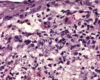

Pemphigus foliaceus (PF) ist die am häufigsten auftretende Autoimmunerkrankung der Haut bei Hunden und Katzen.